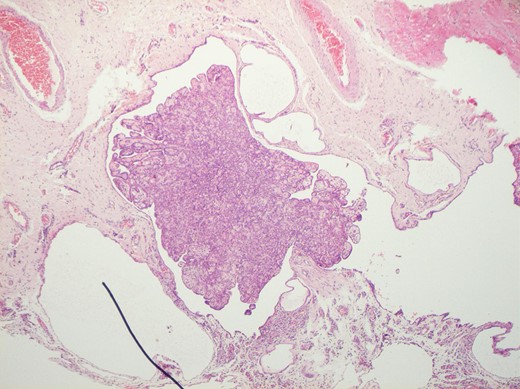

Histological features of the specimen were that of a fibrous cyst wall covered by cuboidal cells with bland nuclei (Fig. 1). Within the cystic space, there were branching, papillary structures with a fibrovascular core, lined with a single layer of bland cuboidal cells (Fig. 2). The stroma was oedematous and hyalinised. No sub-epithelial invasion was seen. There was no unequivocal cytologic atypia or atypical mitosis.

H&E staining of the specimen demonstrating a fibrous cyst wall covered by cuboidal cells with bland nuclei.